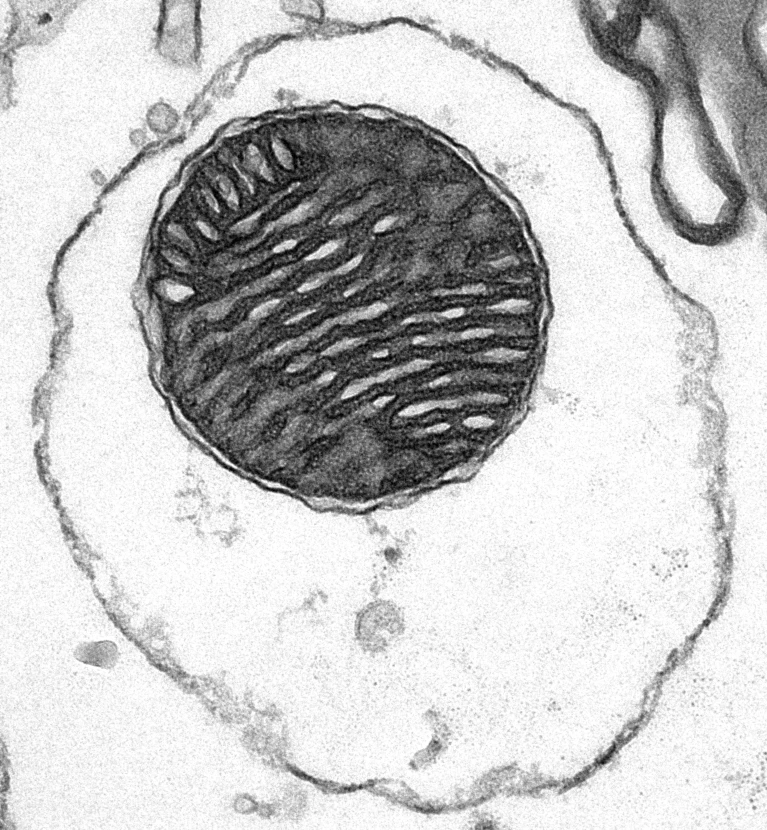

L'administració de mitocondris encoberts (embolicats amb membrana de glòbuls vermells) va prolongar la vida dels ratolins amb una malaltia mortal causada per mitocondris anormals. nature.com/articles/d4158…